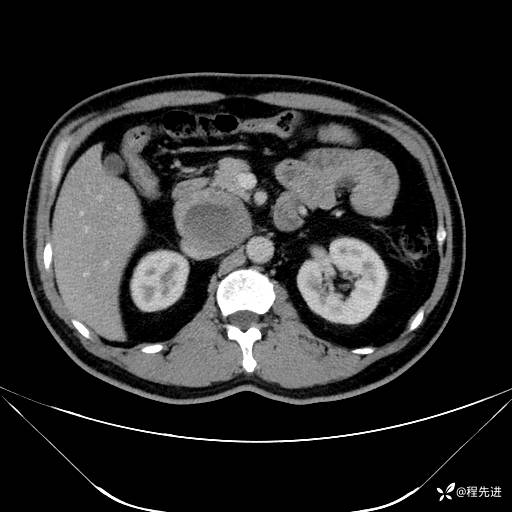

【腹盆】特别精彩病例|发现腹膜后肿物1月余

主诉:发现腹膜后肿物1月余

现病史:患者1月余前查体,行超声检查提示:后腹膜囊实性肿块;慢性胆囊炎伴胆囊内结石;无腹痛腹胀,不伴腹泻发热等;偶感腰背部酸痛。

CT平扫+增强: